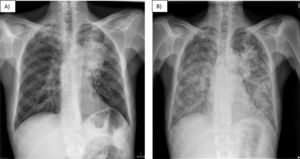

Radiological progress throughout hospital admission. Chest X-ray on admission (A) revealing a lung mass measuring 10cm×5cm causing atelectasis of the left upper lobe, along with apical fibrosis and calcified granulomas. Chest X-ray 14 days after admission (B) revealing bilateral diffuse micronodular interstitial infiltrate not present on the previous X-ray.

The patient's respiratory situation deteriorated, so the X-ray was repeated, showing bilateral diffuse micronodular interstitial infiltrate. The initial suspicion was carcinomatous lymphangitis: the chest CT was not repeated due to respiratory instability.